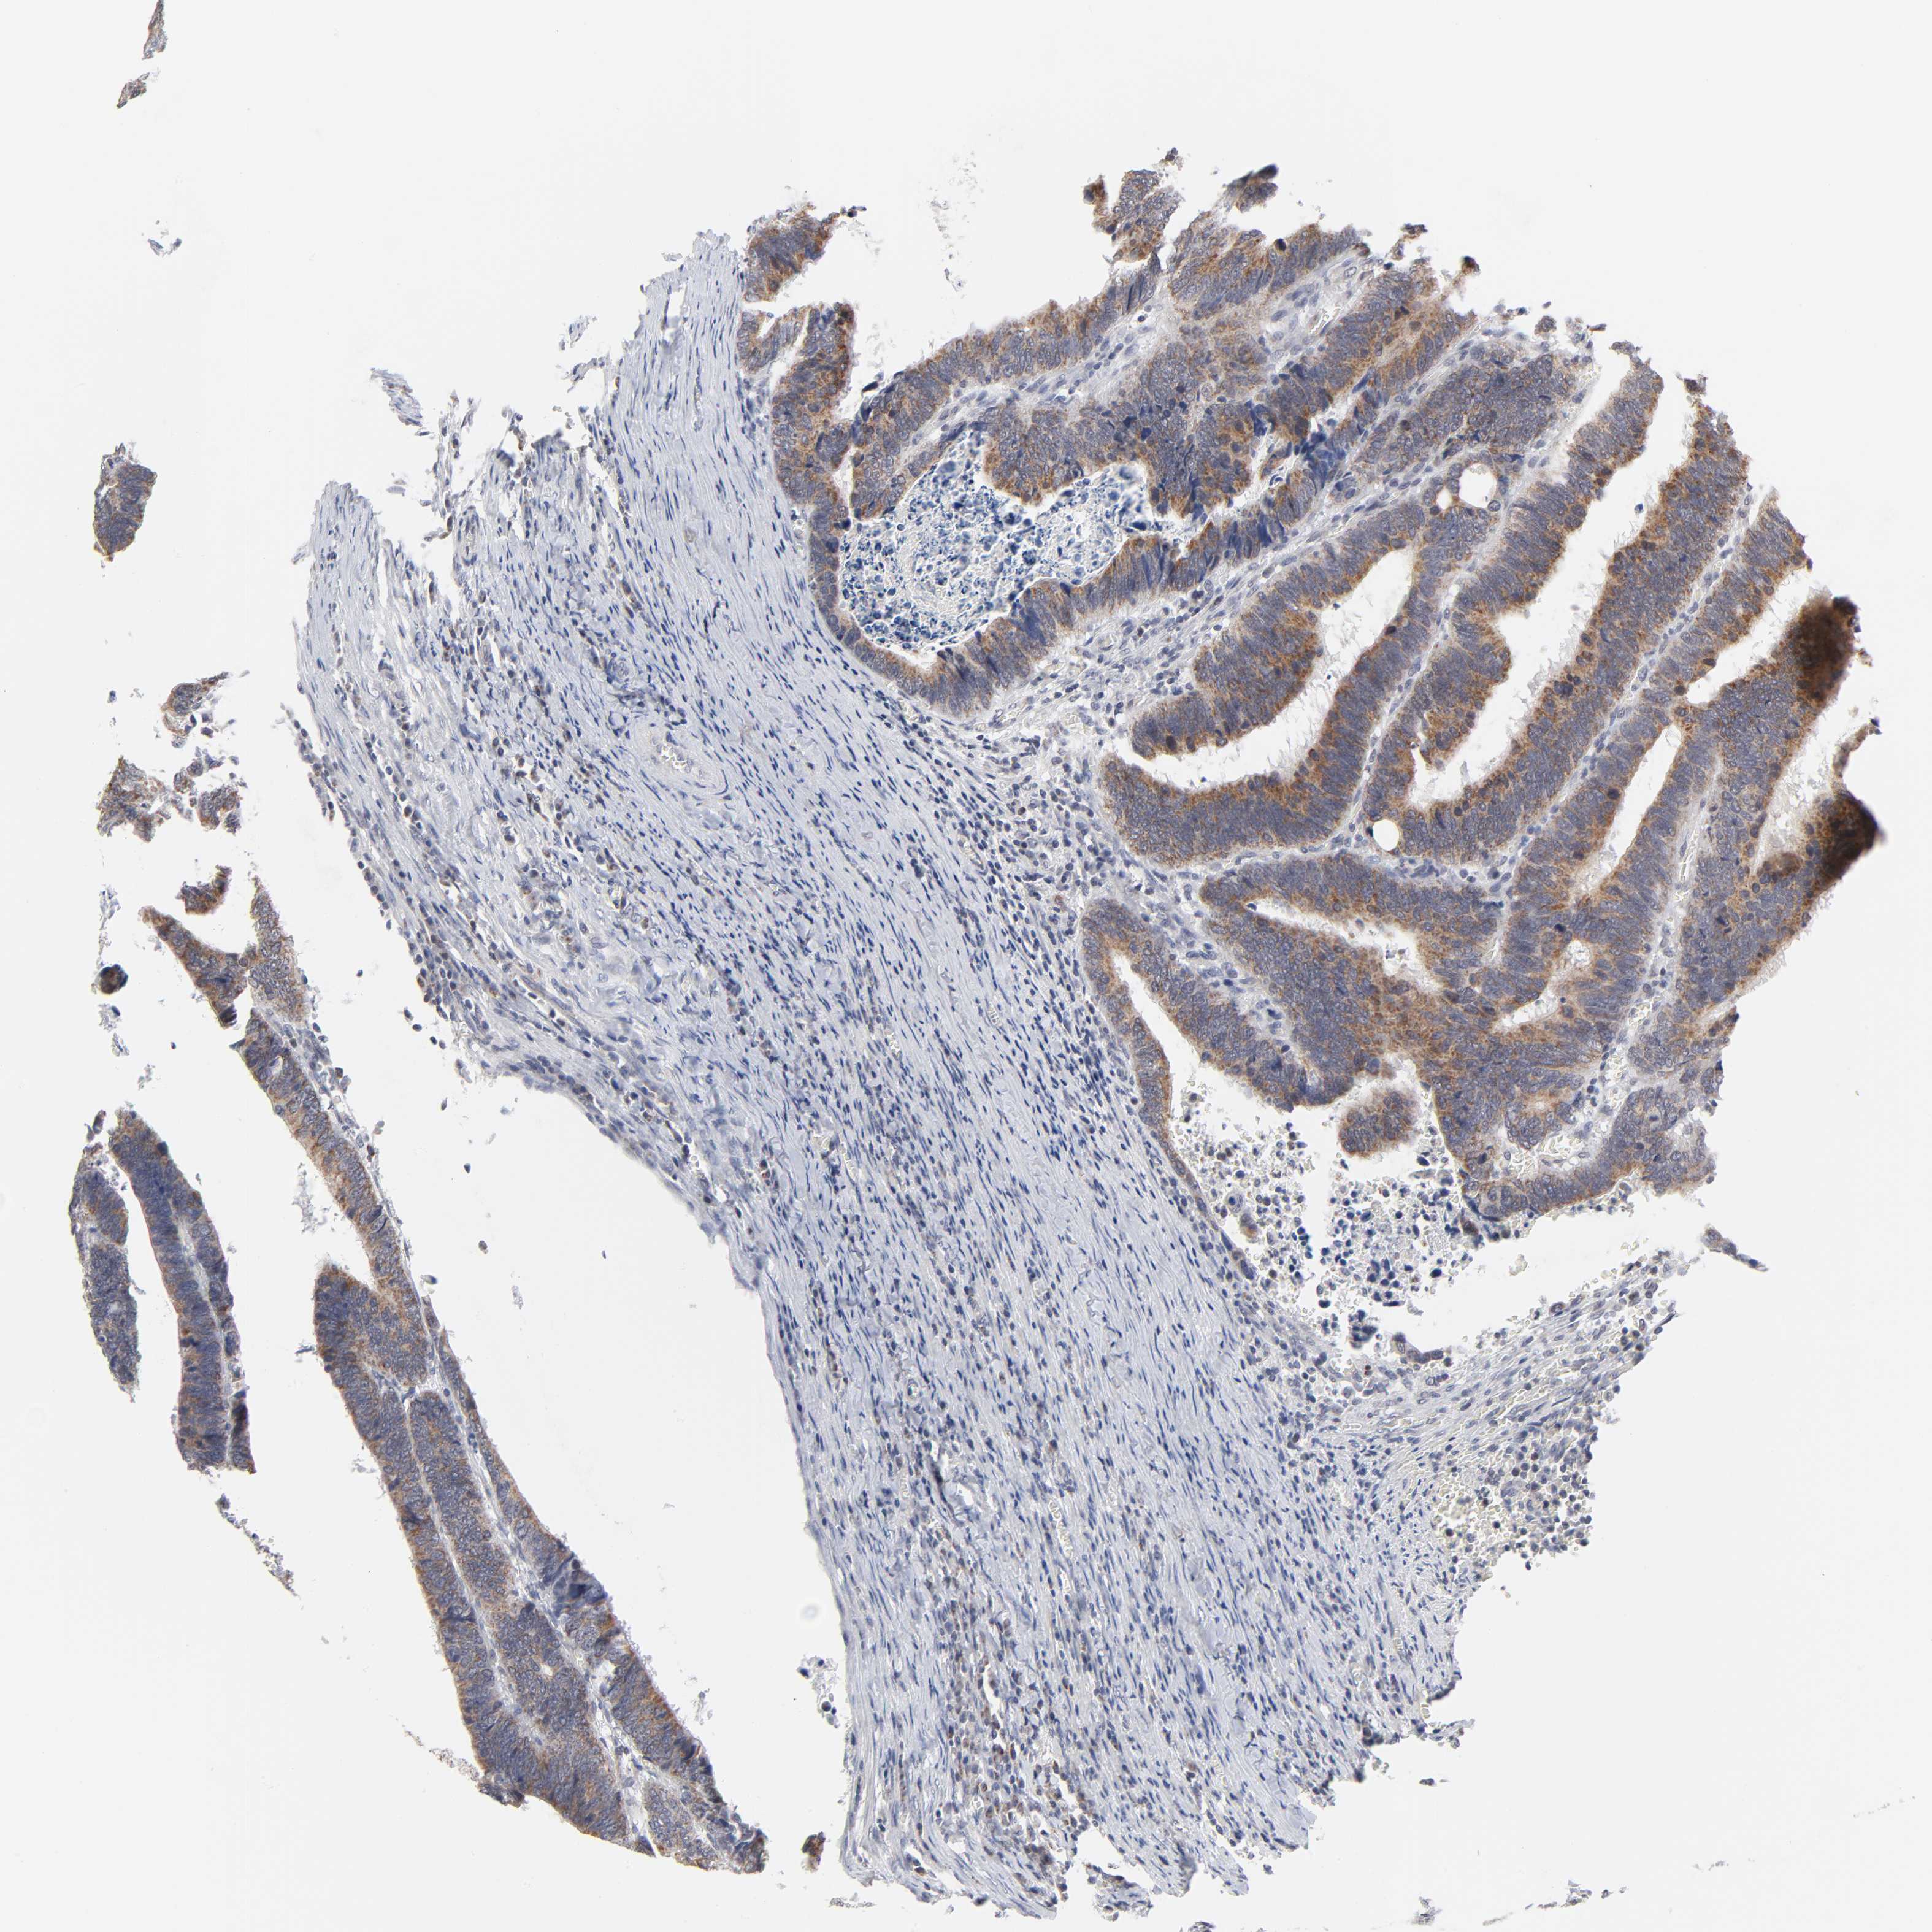

CANCER COLORECTAL CANCER Show tissue menu

ANTIBODIES

AND

VALIDATION